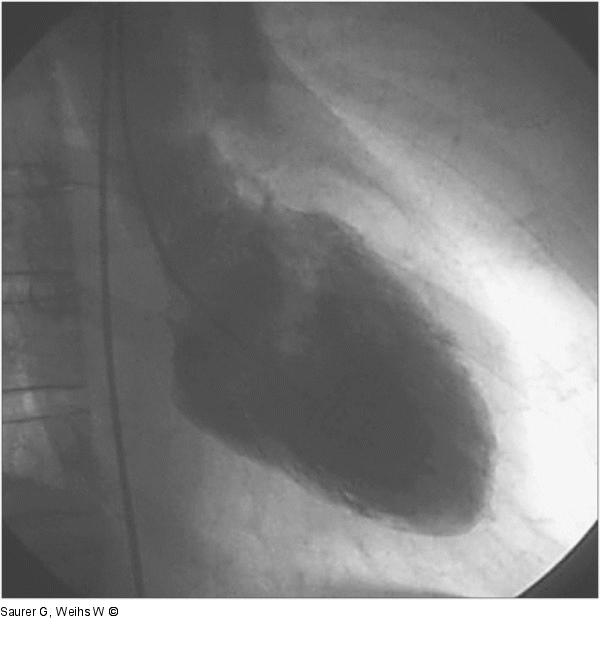

Abbildung 3a: Laevokardiogramm - Diastole - Systole Laevokardiogramm (RAO) in der Diastole (a) und Systole (b). Akinesie der apikalen Segmente ("apical ballooning") mit Hyperkontraktilität der basalen Abschnitte. |

Laevokardiogramm (RAO) in der Diastole (a) und Systole (b). Akinesie der apikalen Segmente ("apical ballooning") mit Hyperkontraktilität der basalen Abschnitte. |